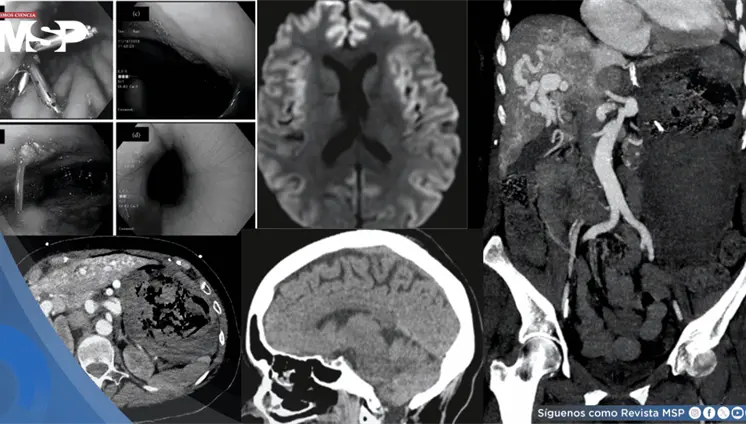

Los hallazgos en resonancia magnética mostraron el patrón característico de edema vasogénico en regiones parieto-occipitales bilaterales.

Las imágenes mostraron una aorta abdominal significativamente dilatada, con un diámetro transversal de 4.4 centímetros, muy por encima del límite normal de 3 centímetros.

Un caso de ruptura de absceso amébico en la vena cava inferior, con un trombo que se extiende hasta la aurícula derecha y tromboembolismo pulmonar tratado con éxito.

El aneurisma, detectado mediante una resonancia magnética, representaba un alto riesgo de ruptura y muerte, lo que obligó a una intervención urgente.